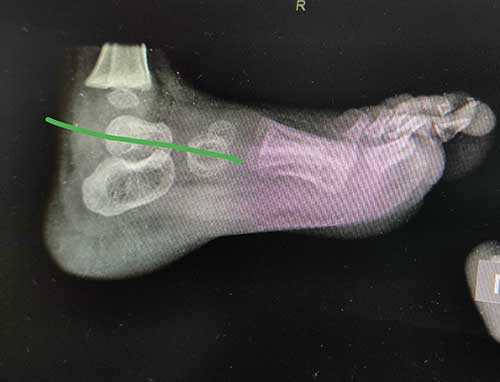

One year After surgery

The goal of surgery is to correct the position of the bones within the foot. This will likely require lengthening tendons or ligaments to allow the bones to be moved. The bones are then held in place with pins and a cast. The pins can usually be removed in the office in 4 to 6 weeks. A special shoe or brace may be recommended to try to prevent recurrence of the deformity. Your doctor will likely recommend follow up visits for a few years to see make sure the foot grows well and doesn’t need additional treatment.